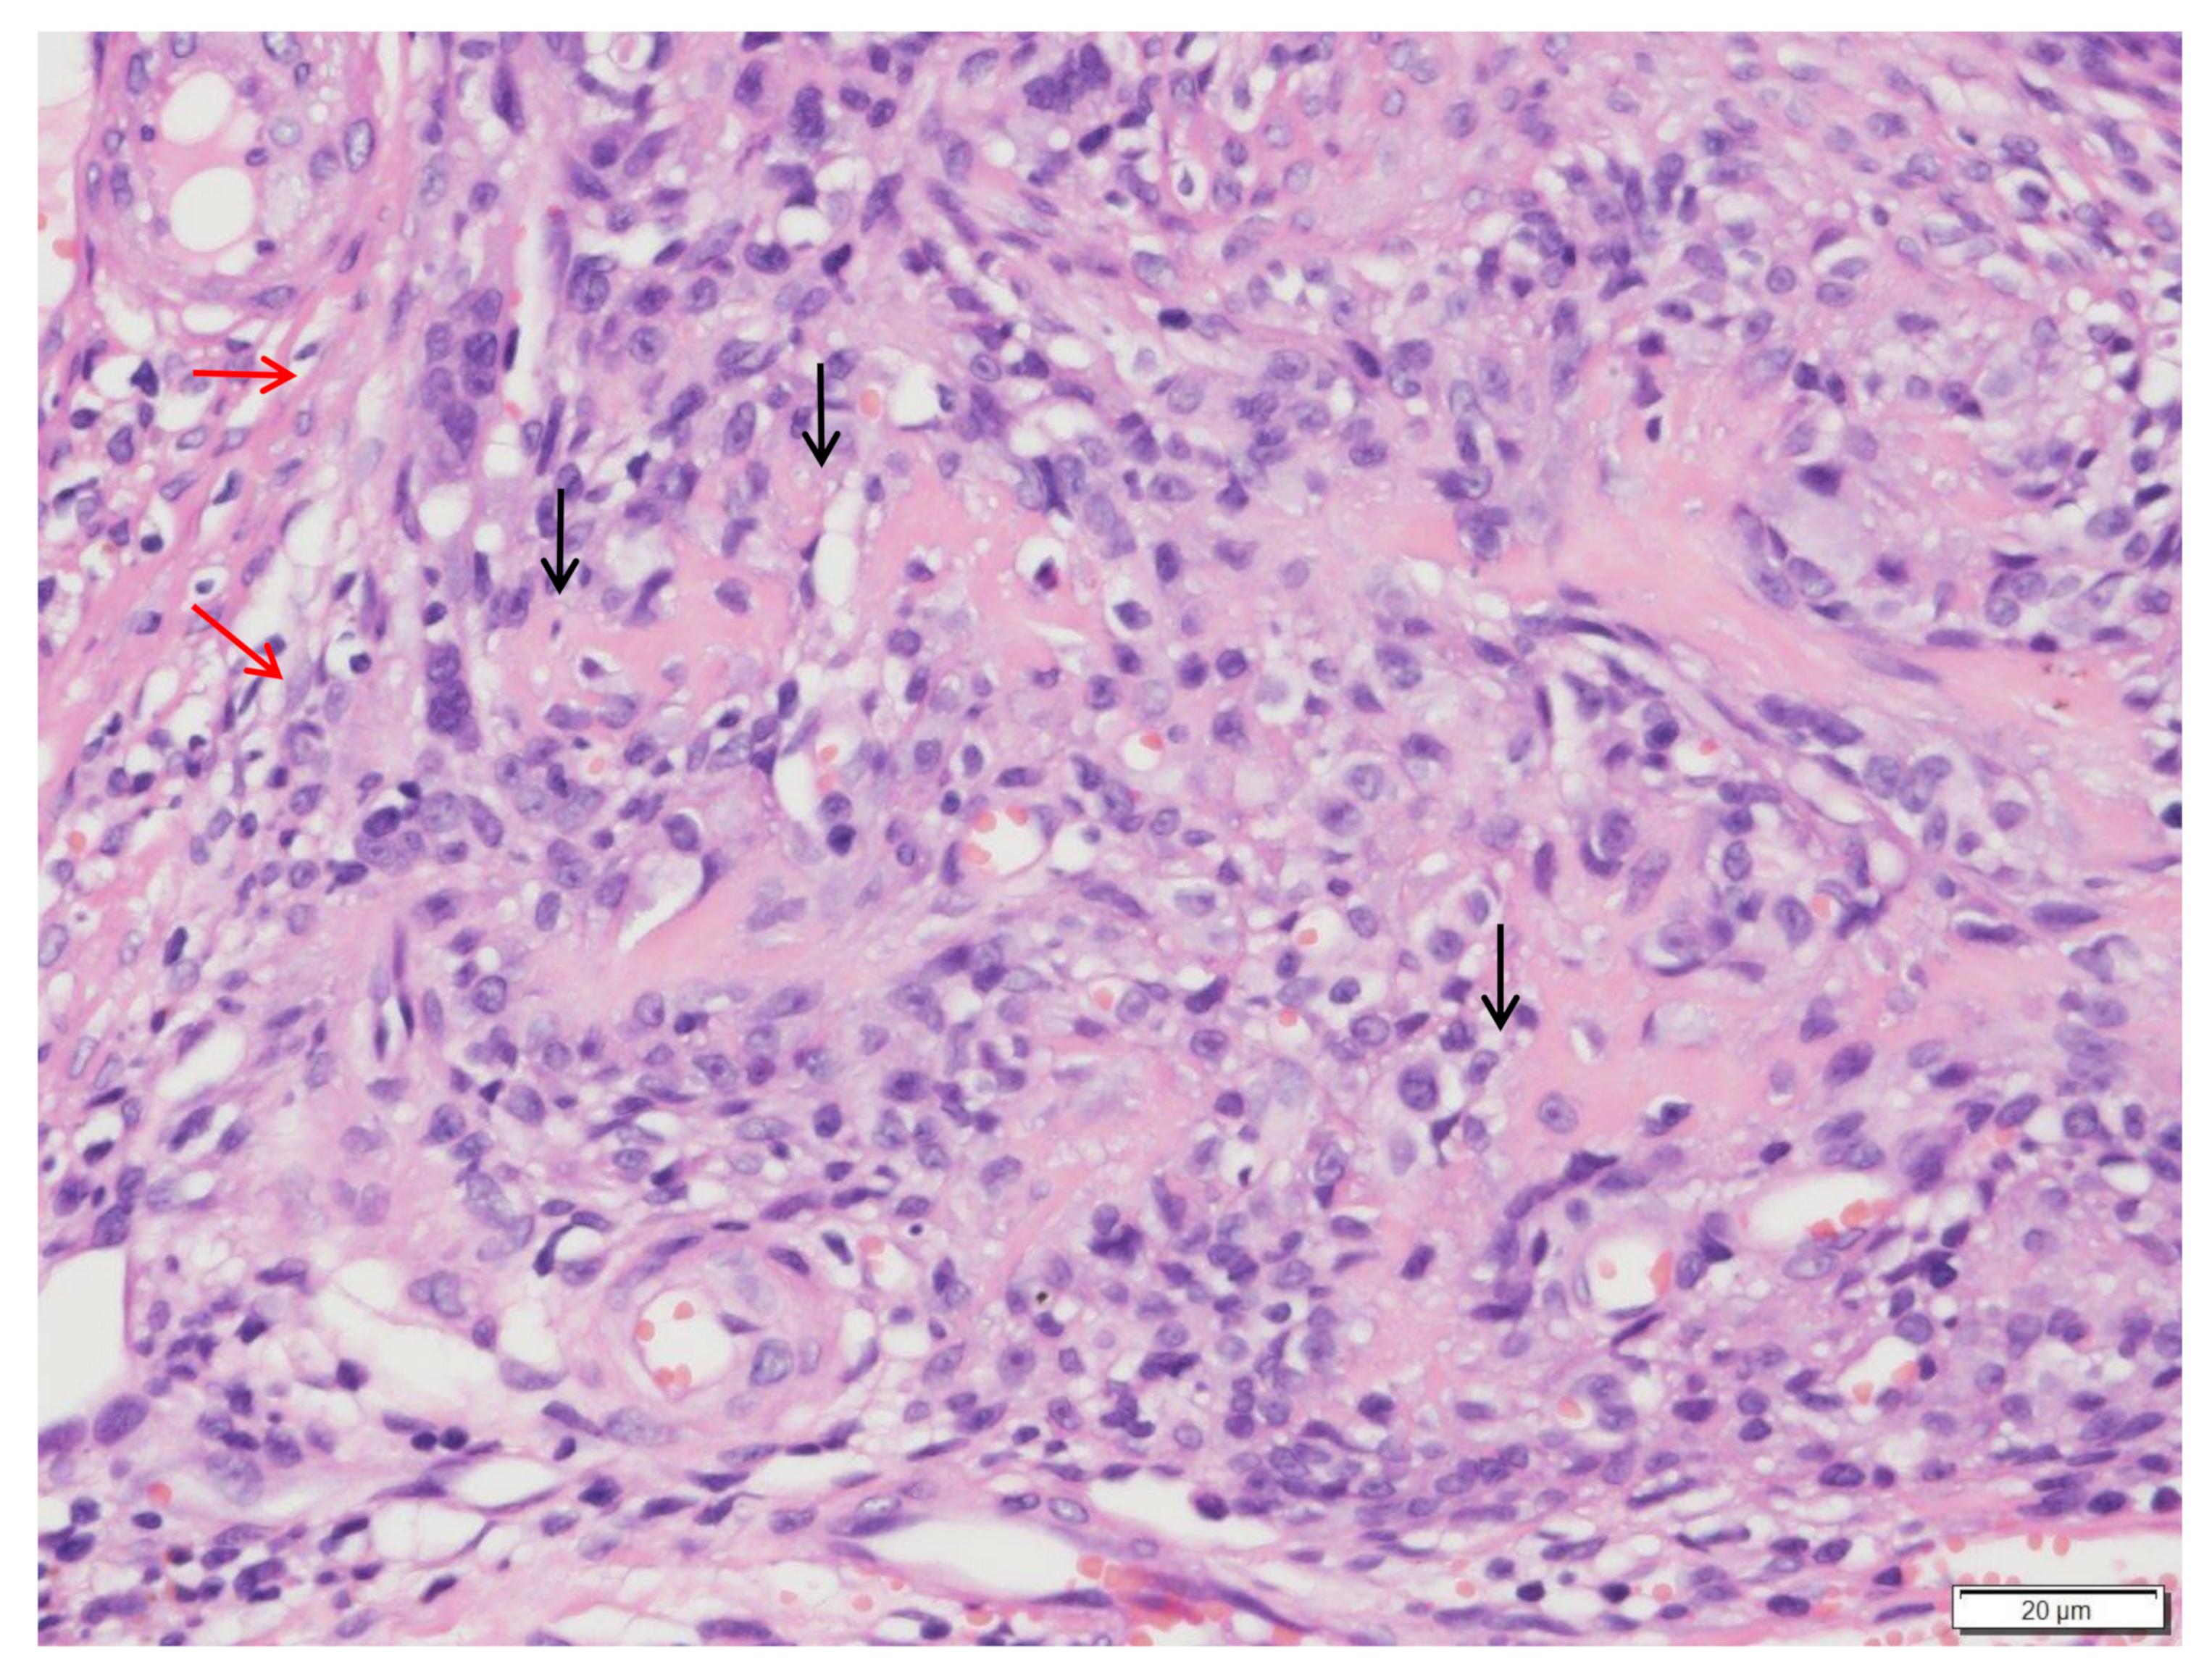

2. Materials and Methods

3. Results